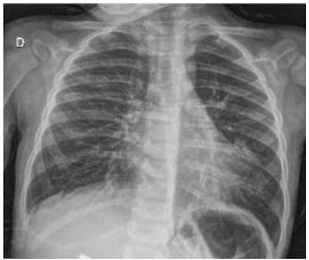

(Arquivo pessoal; imagens usadas com autorização)

Em relação à conduta, assinale a alternativa mais correta.